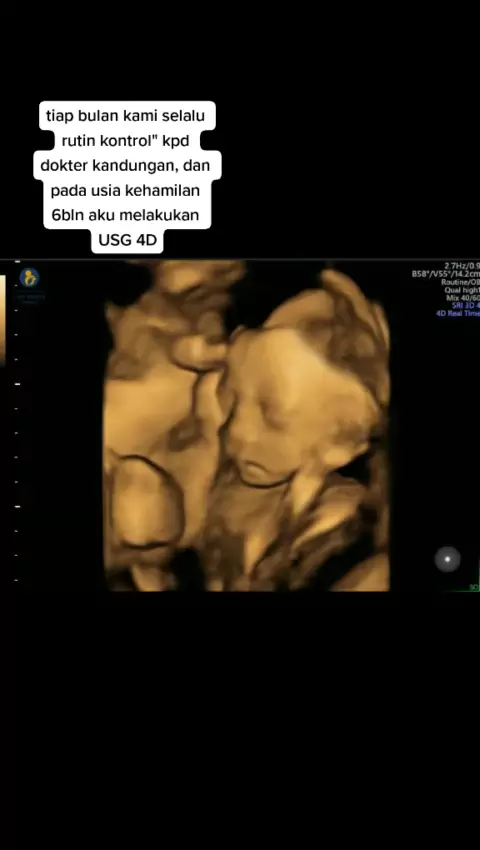

BundaKembar👶👶